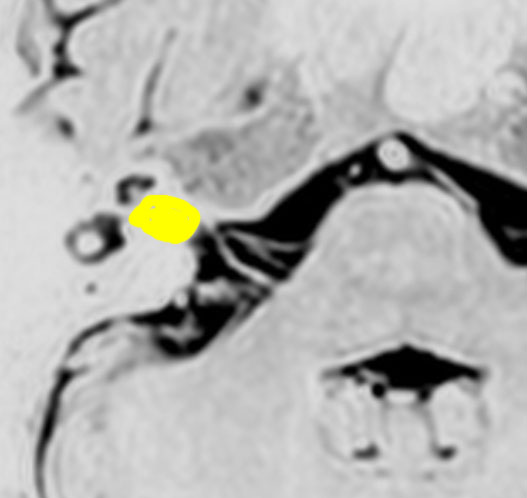

たとえば部分摘出とはどんな感じ?

腫瘍の部分摘出です。手術翌日のMRIです。黄色の矢印の先に白く写っているのがごくわずかな残存腫瘍で,厚さ数mmくらいです。なぜこの部位だけ残すかというと顔面神経がペラペラになっていて腫瘍が外せないからです。このくらい取れると放射線治療を加えないで経過観察します。大きな塊が残ってしまうような部分摘出ではだめです。